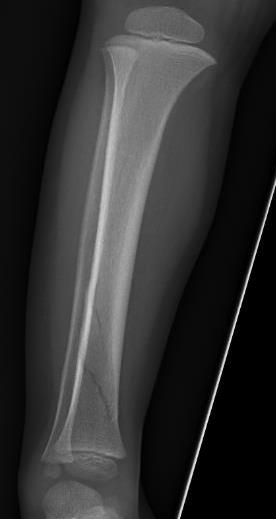

Toddler's Fracture

Definition

Undisplaced oblique fracture of distal tibia

- usually innocuous injury